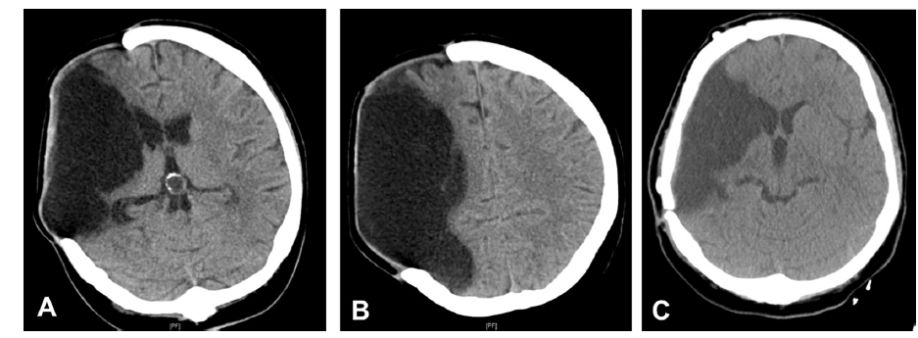

作者回顾性分析该大学医院14例颅骨成形术前接受腰大池引流患者的临床资料。通常在患者颅骨缺损区发现膨隆但没有脑水肿或脑积水征象时,考虑进行腰大池引流术(图1),维持每小时10毫升的脑脊液引流(图2)。在颅骨成形术后立即拔除腰大池引流管。

图1. A、B.女性患者,右大脑中动脉区脑梗死作右额颞去骨瓣减压术,术后5个月的CT成像;C.在腰大池脑脊液引流后完成颅骨成形术,术后1天的CT扫描结果。